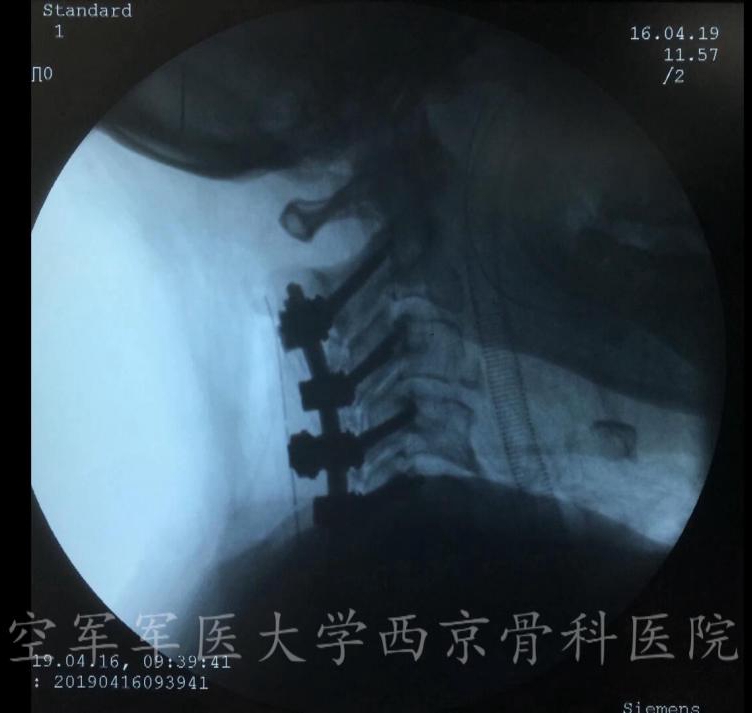

术中X线透视

颈椎后路椎板切除减压,C3-6侧块螺钉、C2椎弓根螺钉固定,植骨融合手术

术中完成减压后置入钉棒系统

术中C臂透视